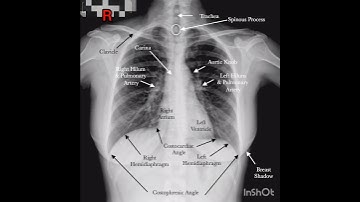

Using digital x-rays and scans to improve diagnosis - part two